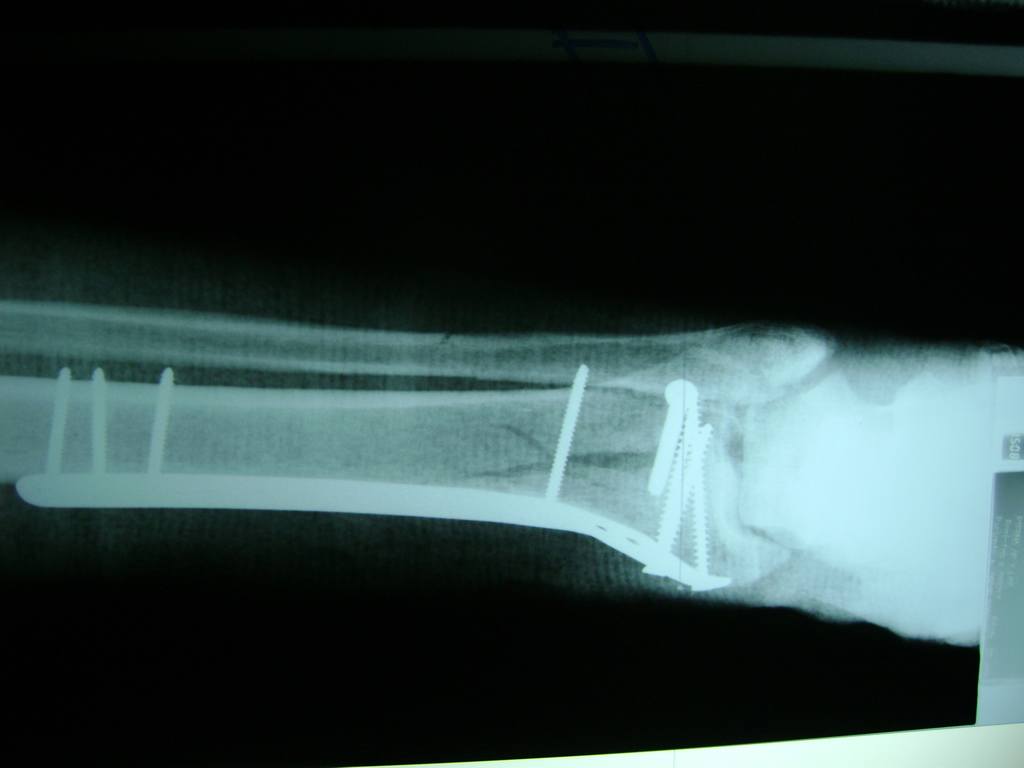

Cirugía de Tibia y Peroné

Aunque cada uno de estos huesos puede fracturarse por separado, normalmente la rotura es una lesión que se produce de forma conjunta

La mayor parte de las roturas implican a la parte proximal del hueso (parte del hueso próximo a la rodilla) o a la parte distal (parte del hueso cerca del tobillo).

Debido a la fina cobertura de piel que recubre la tibia y el peroné, las fracturas generalmente son abiertas, es decir, el hueso roto rasga la piel, atravesándola. Las fracturas de tibia y peroné generalmente se producen por un fuerte impacto o torsión.